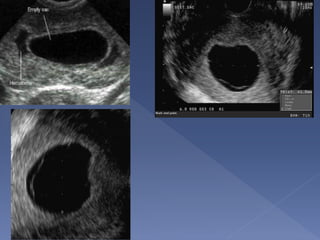

 Direct visualization

of ectopic

pregnancy

 Only seen in 10-20%

pregnancies

 Empty uterus

 Pseudo gestational

sac

 Sac is intra-decidual

 No yolk sac or fetal

pole at sac

diameter of 25 mm

or more

transvaginally

 Sac can be irregular

 Low uterine position

 Weak decidual

reaction

 If unsure repeat in 1

week